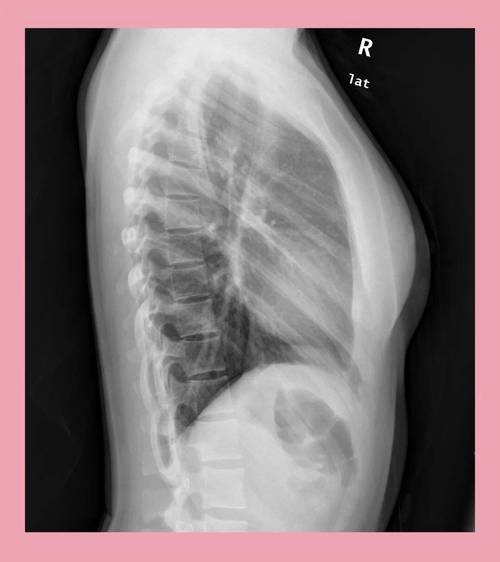

胸部侧位片(LAT)

(图片来源网络,侵删)- 患者体位:患者患侧贴近探测器,双臂上举交叉抱头,避免与胸腔重叠,身体冠状面与探测器平行,胸骨与脊柱分别位于探测器两侧1/3处。

- 中心线与角度:中心线对准腋中线第6胸椎水平,垂直射入探测器,对于肥胖患者,可向头侧倾斜5°-10°,确保膈肌清晰显示。

- 探测器位置:上缘超肩,下缘包膈肌后缘,前缘包括胸骨,后缘包括脊柱。